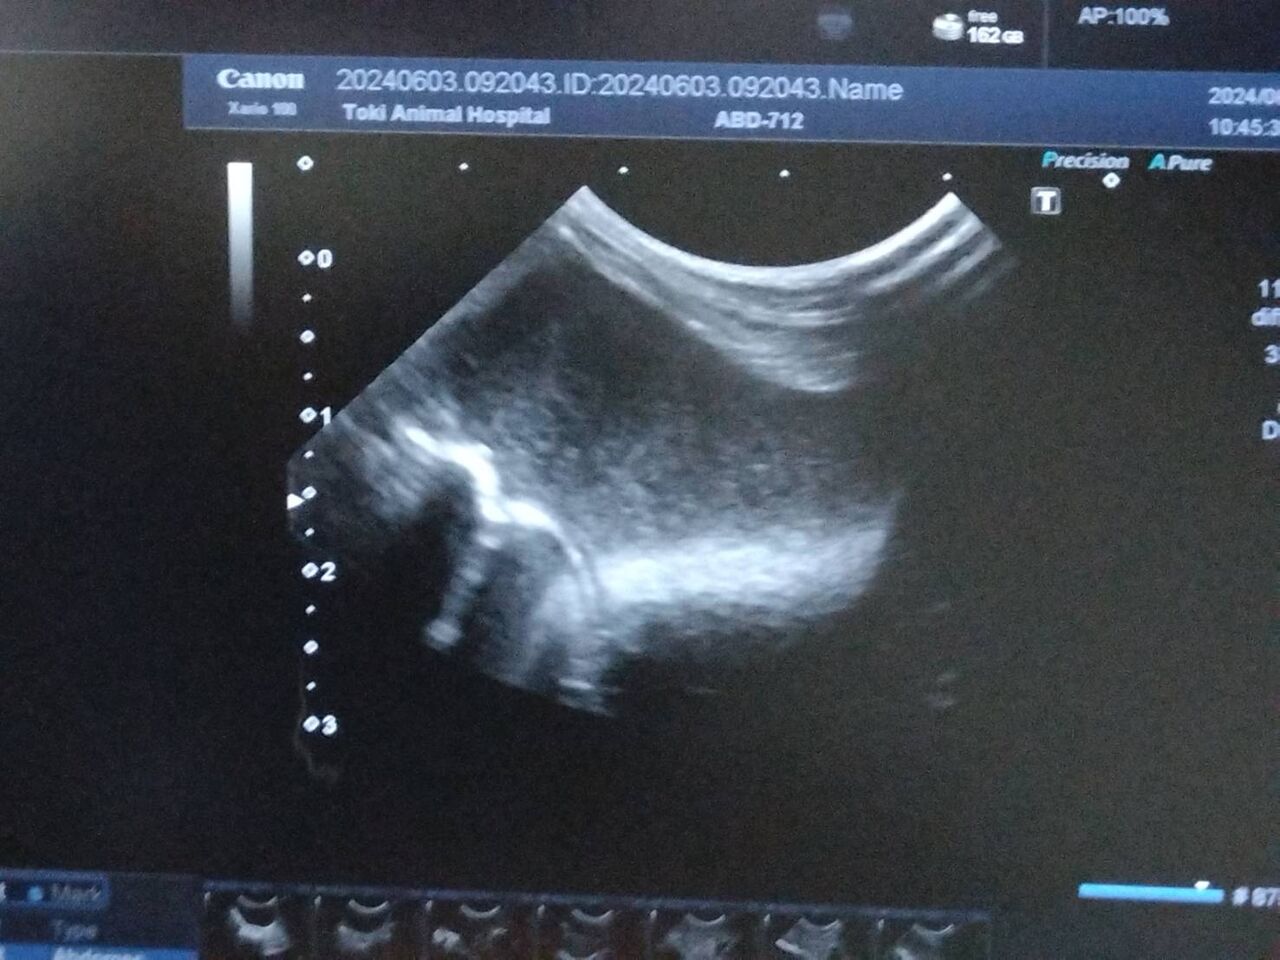

ひかるんくん【師走っこ】

6/2 へやんぽ中に2~3滴ポタポタと血尿ぽいのが3ケ所に出て、陰部を確認しましたが血がついている様子は無し

陰部付近がおしっこで汚れていてハゲている部分もあり

濡らして拭いてみるも、思うように汚れが取れず

6/3 体重1920g 真菌を疑ったが違うとのこと

念のため、膀胱エコー検査をしました

膀胱に砂がたまり尿砂が出て、排尿時に体におしっこがついて汚れているのではないかと予測

お水を飲む量が少ないのでなんとか増やして砂を出していきたい

大換毛中でお尻の汚れ部分の毛は軽く引っ張ると抜けるので、気をつけながら抜くといいとのこと

軽い膀胱炎の可能性もあるのでお薬を出してもらいました